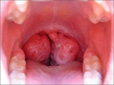

Bademciğe Ne İyi Gelir?Bademcikler, boğazın arka kısmında bulunan ve bağışıklık sisteminin bir parçası olan lenfatik dokulardır. Genellikle enfeksiyonlara karşı savunma mekanizması olarak görev yaparlar. Ancak zaman zaman bademciklerde iltihaplanma ve enfeksiyon görülebilmektedir. Bu durum bademcik iltihabı (tonsillit) olarak adlandırılır. Bademciğe iyi gelen bitkiler ve doğal yöntemler, bu rahatsızlığın tedavisinde yardımcı olabilir. Bademciği Rahatsız Eden BelirtilerBademcik iltihabının başlıca belirtileri şunlardır: